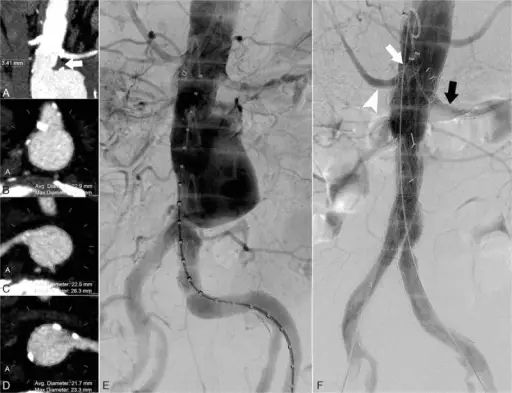

Abdominal Aortic Aneurysm

Abdominal aortic aneurysm (AAA) is an aneurysm of the abdominal aorta.

Abdominal aortic aneurysm typically develops above the aortic bifurcation but below the renal arteries.

Abdominal aortic aneurysm (AAA) is typically associated with hypertension and atherosclerosis.

Abdominal aortic aneurysm (AAA) typically presents with a triad of:

Symptoms of abdominal aortic aneurysm include an abdomen lump that pulses initially and enlarges over time.

Complications of abdominal aortic aneurysm (AAA) include:

- Rupture, especially when the diameter is greater than 5 cm

- Compression of nearby structures (such as the ureter)

- Thrombosis

- Embolism